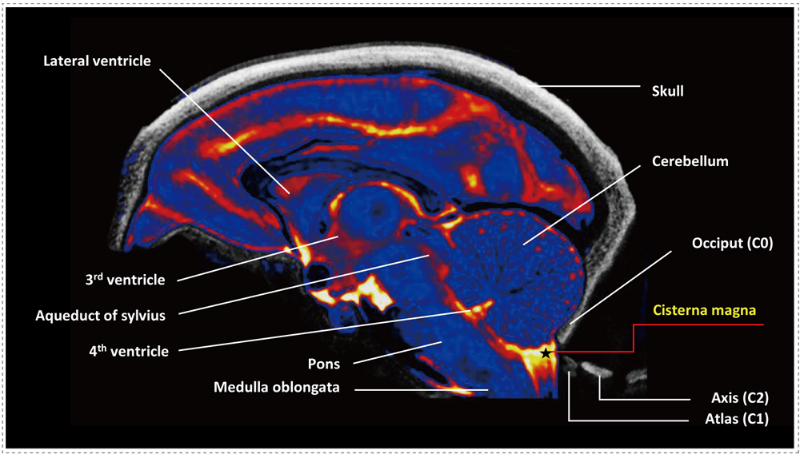

小腦延髓池常被用於(yu) 采集腦脊液和中樞給藥等治療。而近年來小腦延髓池內(nei) 注射已被開發用於(yu) 增強中樞神經係統藥物輸送。隨著核酸類藥物的開發突飛猛進,多款藥物陸續獲批上市。寡核苷酸及AAV新藥研發臨(lin) 床前體(ti) 內(nei) 藥理麵臨(lin) 兩(liang) 大挑戰,如何有效地將這類新分子遞送到靶器官組織,如何解決(jue) 安全性問題。而小腦延髓池內(nei) ICM注射就可以有效遞送定向大腦的寡核苷酸。

猴腦中小腦延髓池-(CM)-的定位示意圖.jpg

猴腦中小腦延髓池 (CM) 的定位示意圖[1]